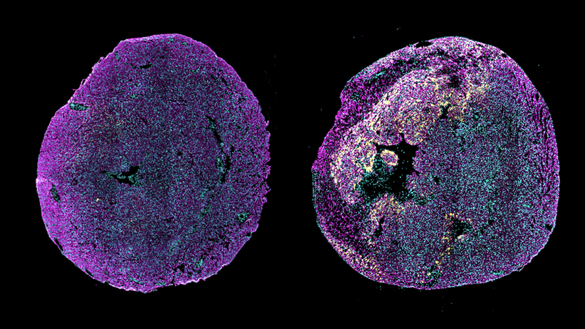

Imagine obţinută printr-o tehnică de laborator care foloseşte markeri fluorescenţi pentru a evidenţia anumite structuri sau proteine din ţesut. Aici imunofluorescenţa se vede la nivelul unor secţiuni transversale de inimă, provenite de la un şoarece nou-născut, sănătos (stânga), sau de la un şoarece nou-născut la care infarctul miocardic a fost indus în prima zi după naştere, analizat la 3 zile după leziune (dreapta). Semnalul galben indică niveluri ridicate de expresie a pro-ANP în zona de margine a miocardului afectat. Pro-ANP este o proteină care răspunde la leziune şi contribuie la repararea inimii la şoarecii neonatali. Cardiomiocitele sunt evidenţiate în magenta (α-actinină), iar nucleii celulari sunt marcaţi în cyan. Sursa: Cheng Lab / Columbia University, martie 2026

Pentru a înţelege diferenţele, echipa a comparat şoareci nou-născuţi şi adulţi după infarct. La nou-născuţi, activitatea genei Nppa, care produce precursorul ANP, a crescut de peste 25 de ori. La adulţi, creşterea a fost de aproximativ zece ori, posibil insuficientă pentru repararea ţesutului afectat. Blocarea acestei gene la nou-născuţi a redus semnificativ capacitatea de vindecare a inimii.